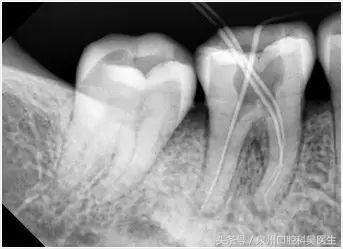

为什么根管治疗需要拍多张牙片?

在进行根管治疗的时候,拍牙片是必须要的程序的,并且至少要保证3张牙片。

第一张在根管治疗前,拍片可以帮助医生更准确了解牙根的基本情况,以制定治疗计划;

第二张在根管治疗中,可以帮助医生了解治疗的情况,比如根管预备是否到位,方便制定下一步治疗方案;

第三张是在根管治疗结束后,帮助判定根管充填质量,以及治疗效果,发现问题及时补救。